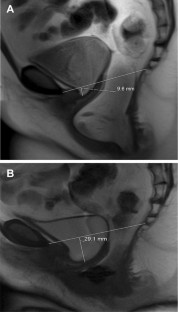

Fig. 1